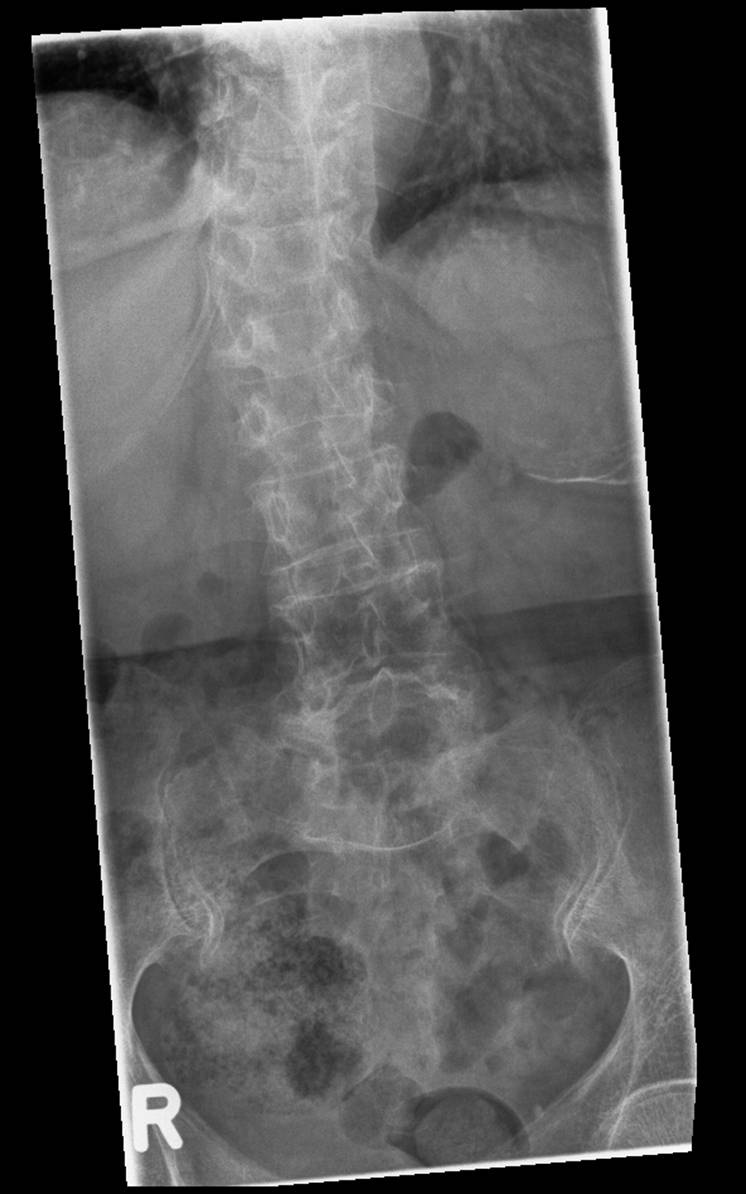

> Пациентка, 1934 г.р., постует 8 апреля к травматологам... упала дома на

> спину... сильные боли в области перехода грудного в поясничный отдел

> позвоночника... Рентген... (первые две картинки)

> там вроде компрессионный перелом, но толи свежий, толи старый... не совсем

> понятно...

> Выполняют КТ-позвоночника... (Третья и четвертая картинки)

Какая-то округлая тень над левой почкой, причем не только по СТ это видно.

Может это и есть основной причиной болей?